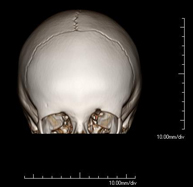

- Neurorradiología- TC Cráneo Prueba radiológica que consiste en obtener imágenes del cráneo de alta definición anatómica (tronco cerebral, cerebelo, cerebro, calota craneal, etc.), mediante el empleo de un equipo de TC (Tomografía Computarizada).Indicaciones: traumatismos, cefalea, trastornos de la memoria, pérdida de fuerza súbita en una extremidad o mitad del cuerpo. Prueba radiológica que consiste en obtener imágenes del cráneo de alta definición anatómica (tronco cerebral, cerebelo, cerebro, calota craneal, etc.), mediante el empleo de un equipo de TC (Tomografía Computarizada).Indicaciones: traumatismos, cefalea, trastornos de la memoria, pérdida de fuerza súbita en una extremidad o mitad del cuerpo.

- TC Macizo facial  Prueba radiológica que consiste en obtener imágenes del macizo facial (cara) de alta definición anatómica mediante el empleo de un equipo de TC (Tomografía Computarizada). Indicaciones: tumores, cirugía plástica. Prueba radiológica que consiste en obtener imágenes del macizo facial (cara) de alta definición anatómica mediante el empleo de un equipo de TC (Tomografía Computarizada). Indicaciones: tumores, cirugía plástica.